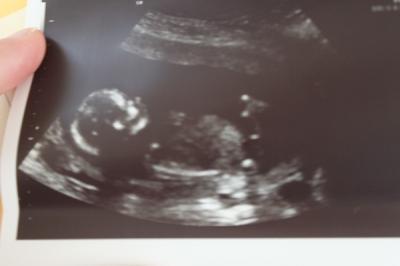

so jetzt berichte ich auch noch schnell von meinem Termin gersten ich war gestern bei der ersten grossen VU ( 13+0) und ich muss sagen mir ist ein grosser stein vom herzen gefallen , ich bin überglücklich und kann nun endlich alles geniessen ich hab ein perfektes kleines baby gesehen und man konnte schon so viel erkennen, die magenblase, die harnblase , die kieferpartie, das gehien , das herzchen , füsschen und hänchen , nase und mund einfach faszinierend für uns war natürlich einer der wichtigstens sachen eine geschlossene wirbelsäule und beinaktivitäten ( wir haben ja einen sohn mit spina bifida) das neuralrohr ist geschlossen die beinchen bewegen sich , die nackenfalte ist absolut in ordnung , magen und harnblase sind gefüllt ... es sieht alles sooo toll aus und dann bekamen wir auch noch ein outing , versteifen sollen wir uns noch nicht darauf aber es sieht sehr nach einem jungen aus , gezeigt hat sie es uns auch :D bin gespannt ob es dabei bleibt :D lg katrin

Bild zu mein FA termin gestern - Forum für August - Mamis

herzlichen glückwunsch. ist ein sehr süßes bild von eurem vielleicht jungen. freu mich:)... hoffe auch das ich in zwei wochen vielleicht erfahre was es wird bin schon ganz gespannt. wünsch euch noch einen schönen abend

Glückwunsch, das sind tolle Nachrichten, dass bei Deinem Baby Alles gut ist! Das freut mich sehr für Dich! Ein wundervolles Bildchen hat Du da mit nach Hause bekommen :-) ! Schön,dass sich Dein Krümel schon geoutet hat... ich muss noch 3 Wochen warten :-( ! Hoffe ich erfahre, dann auch, wer da in meinem Bauchi rumturnt ! :-)) L G Mone